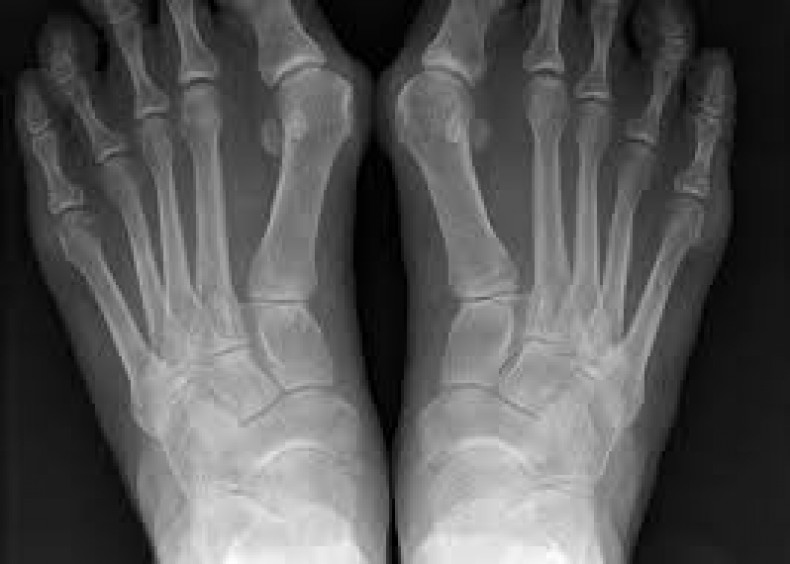

Шишка на нозі, бурсит або вальгусна деформація першого пальця – найчастіша патологія стопи. Розвивається внаслідок відхилення великого пальця у бік інших, що супроводжується травматизацією суглоба. У відповідь на травму на ньому утворюється кістковий нарі

• Викривлення великого пальця, зміна його положення стосовно анатомічної осі та інших пальців стопи.

• Формування шишки, мозолі в ділянці випираючої кісточки суглоба.

• Почервоніння, набряк, припухлість "кісточки".

• Біль, печіння у суглобі внаслідок запалення бурси (суглобової сумки, заповненої синовіальною рідиною) – при ходьбі, носінні тісного взуття.

• Причини: Компесаторне вкорочення мяза. який відповідає за розгинання великого пальця ноги.